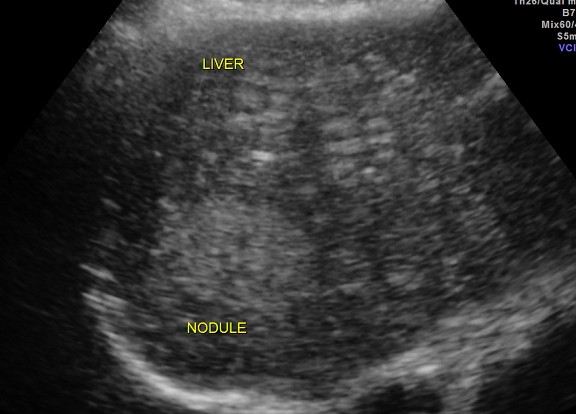

CT scan of the abdomen confirmed the findings ; For further clarification PET whole body scan was done at a centre in Chennai. The following images are from that.

Extensive FDG avid hepatic metastases involving both lobes.

The biopsy report of the liver secondary was a poorly differentiated carcinoma.